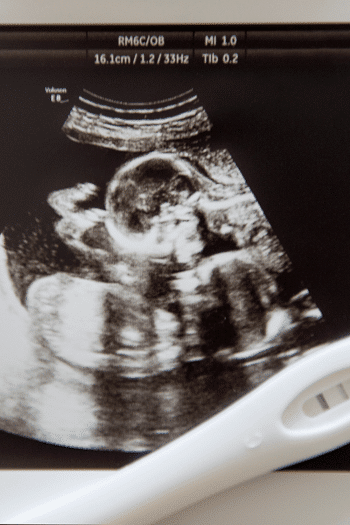

If you’re like me you may not have even known you were pregnant until you were more than 10 weeks along. You may have gone to your first appointment in shock and with a good amount of anxiety somewhere around 10 weeks. A routine first OB appointment may have been met with some mumbling and a bit of concern as they squeezed you into the ultrasound schedule down the hall to confirm twins.

Your first twins ultrasound is usually the best time to ask what type of twins you are having. This is often referred to as your dating scan. During this scan, the technician may or may not be able to tell if you are carrying twins who share a placenta and/or sac.

Typically your first ultrasound will confirm your twin pregnancy. This is often called your dating scan and usually takes place at around 10 weeks along. Of course, if you are an infertility mama, you will probably have a scan earlier on and may be able to see your twinnies at 6 or 7 weeks. This would be the first of many twin ultrasound appointments!